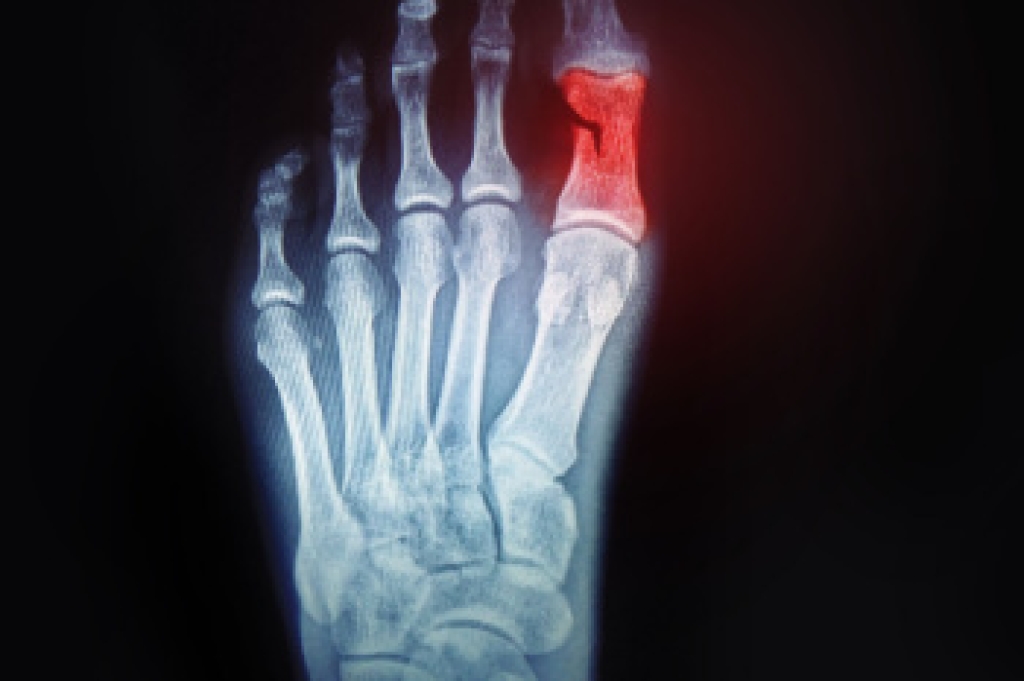

Although most people try to avoid foot trauma such as banging, stubbing, or dropping heavy objects on their feet, the unfortunate fact is that it is a common occurrence. Given the fact that toes are positioned in front of the feet, they typically sustain the brunt of such trauma. When trauma occurs to a toe, the result can be a painful break (fracture).

Severe toe fractures may be treated with a splint, cast, and in some cases, minor surgery. Due to its position and the pressure it endures with daily activity, future complications can occur if the big toe is not properly treated.